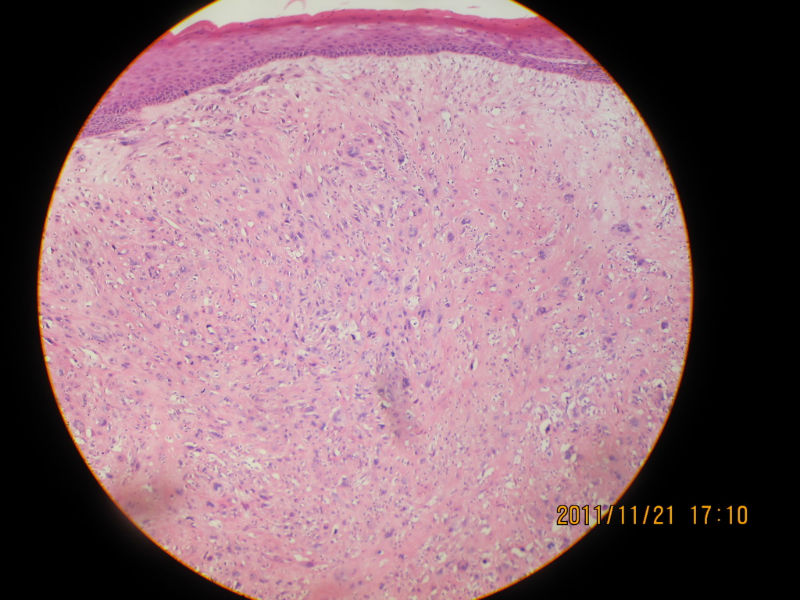

男性,82岁,声带肿物

图1

图2

图3

图4

图5

图6

图7

图8

图9

图10

图11

图12

图13